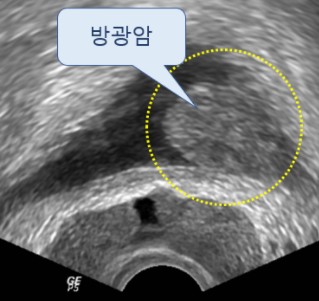

- 소변에 피가 섞여 나옴 (혈뇨)

- 설명: 암이 진행되어 요도나 방광 경부를 침범했을 경우 소변에 피가 섞여 나오는 혈뇨가 나타날 수 있습니다. 하지만 이는 암이 어느 정도 진행된 후 나타날 수도 있고, 방광염이나 요로결석 등 다른 질환으로도 발생할 수 있습니다.